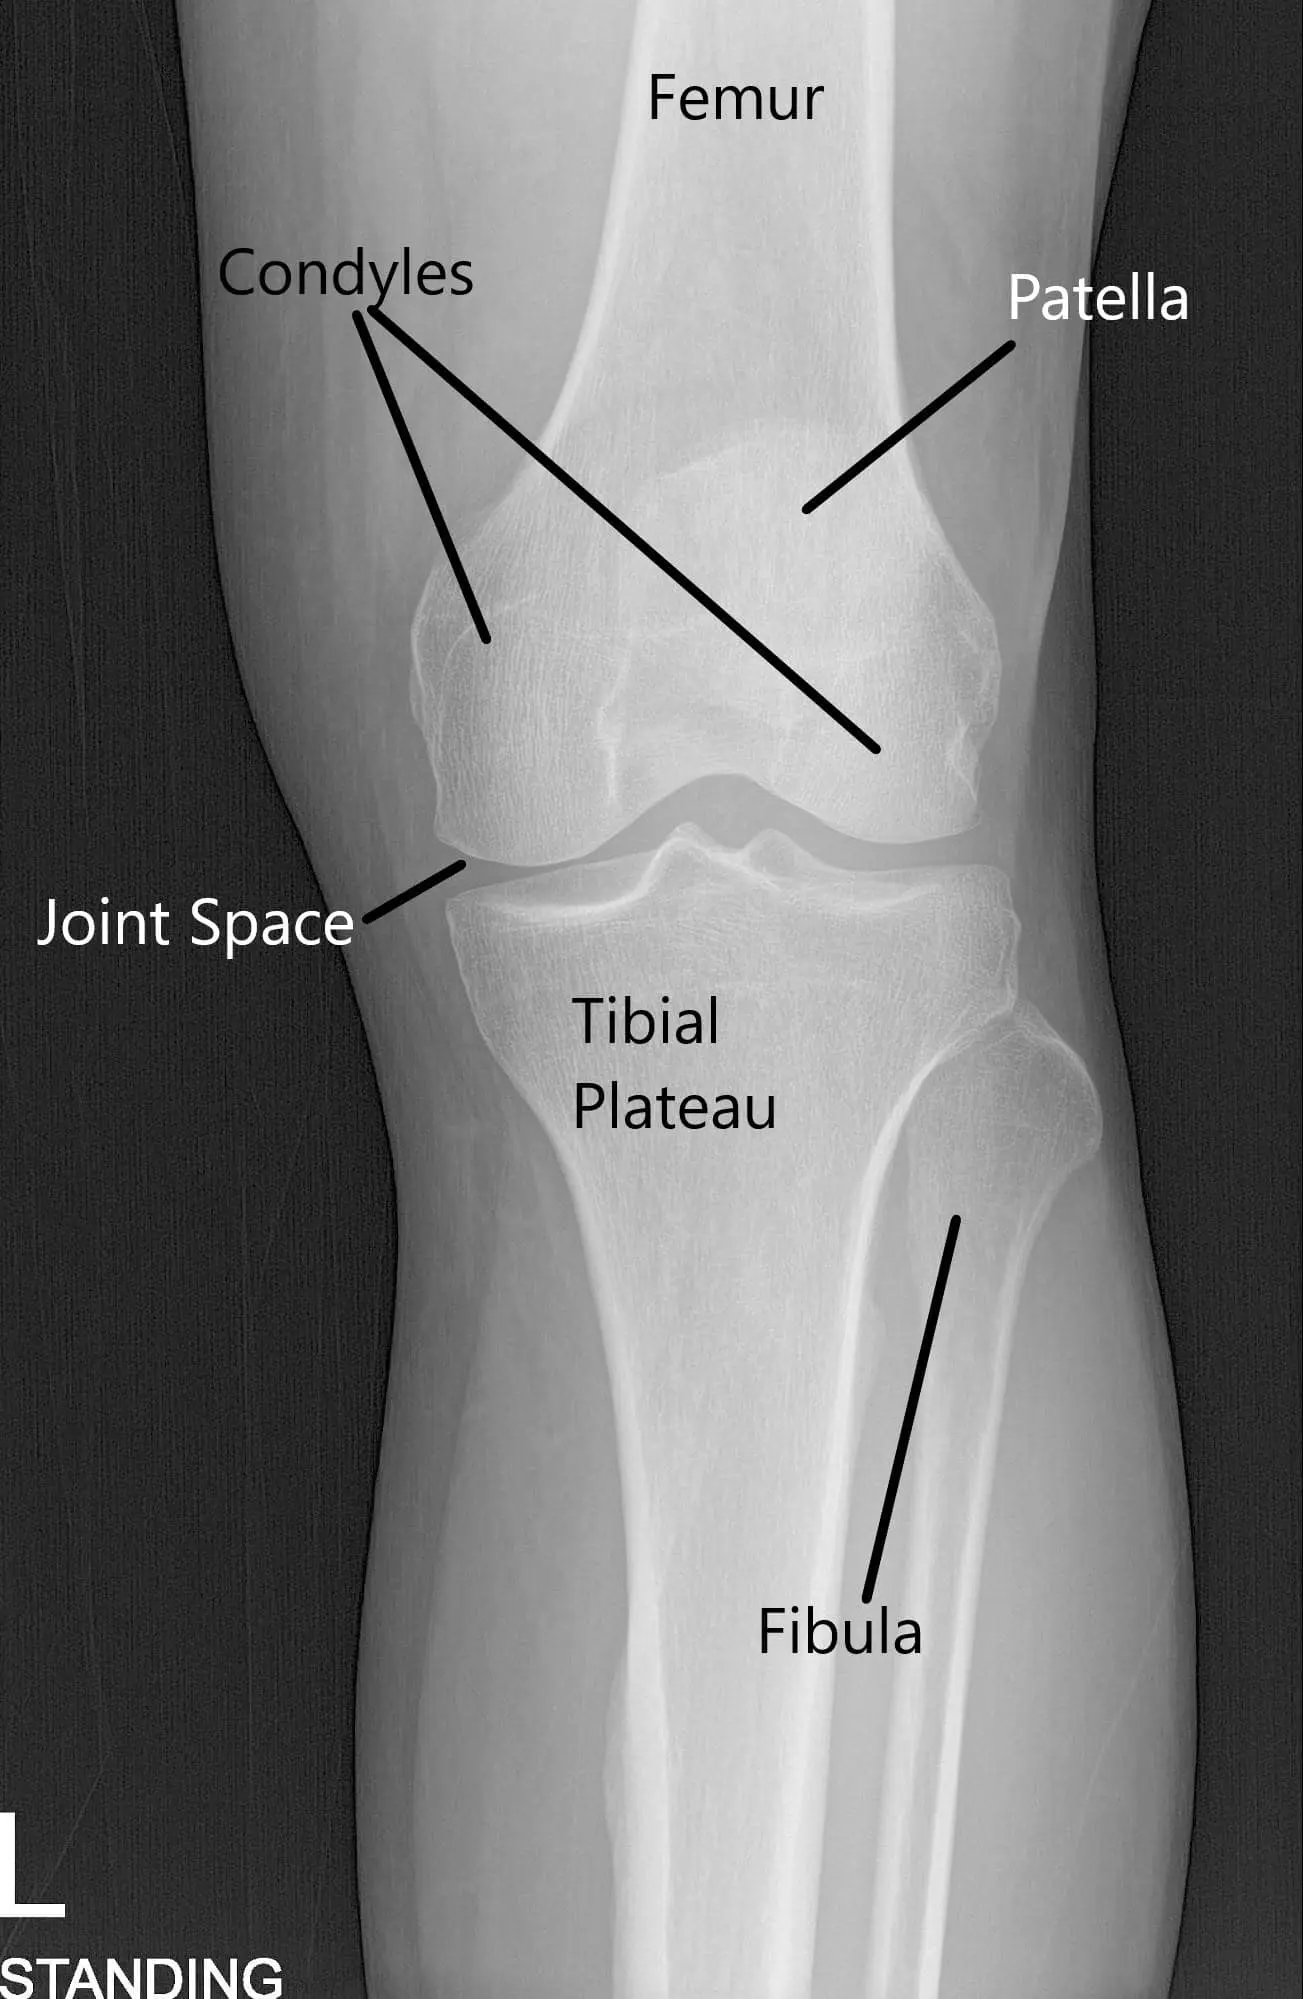

X-ray of the knee in AP and skyline view.